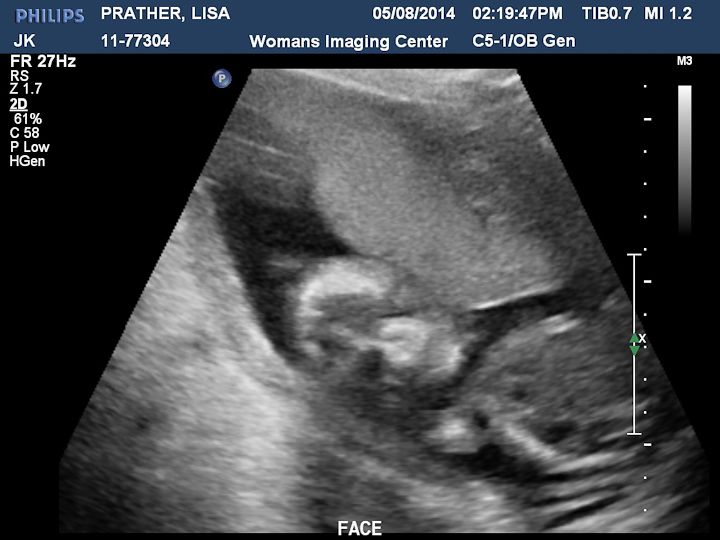

Here are some pictures we got. There is a description on each picture of what you are looking at.

The baby was moving a lot and kept turning it's head right towards us.

This is a 3D shot of the face.